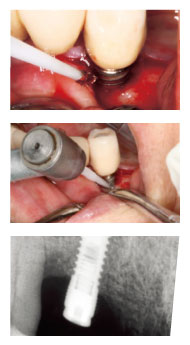

症 例

【CASE1】

右下7 インプラント周囲炎

歯肉を剥離し、掻爬。

露出しているインプラント体表面をiBrushにて研磨し、汚染物質を機械的に取り除く。

処置前

切開、剥離時

iBrushにてインプラント体表面を研磨

研磨後